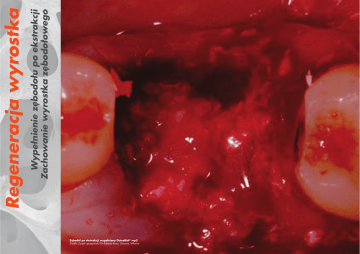

Wypełnienie zębodołu po ekstrakcji

Zachowanie wyrostka zębodołowego

Zębodół po ekstrakcji wypełniony OsteoBiol® mp3

Źródło: Dzięki uprzejmości Dr Roberto Rossi, Genova, Włochy

Ryc. 6 Pole przed wszczepieniem biomateriału

Ryc. 7 Pole po wszczepieniu biomateriału